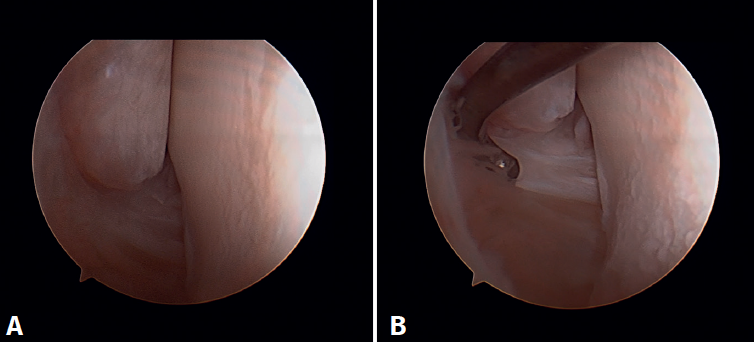

Surgical technique: arthroscopic treatment of acute medial complex injuries

In terms of surgical technique, the working portals are established in the same way as in conventional ankle arthroscopy: one anteromedial portal and one anterolateral portal. We always start with diagnostic arthroscopy to confirm the injury to the deltoid ligament. A probe can be used to verify the laxity of the fibers, and a test can be performed by inserting the probe through the medial groove: the lesion is confirmed if the instrument passes through. For repair, the viewing portal will be the anterolateral portal, thus allowing us to work more directly through the anteromedial portal. The anterior fibers of the superficial tibiotalar and intermediate fibers of the deep portion of the deltoid ligament are the ones that can be repaired with the arthroscopic technique(38). Once the ligament has been identified and dissected, a suture is passed between the fibers using a suture passer. The medial malleolus anchorage zone is prepared with a shaver or a small burr. With the ankle in neutral position, the anchor is inserted while maintaining the tension of the sutures. The intersection of the line parallel to the tibiotalar joint and a perpendicular line marked from the tip of the malleolus and along the lateral border of the malleolus can be used as an anatomical reference for placement(21). After reduction, we again test the fibers for tension and passage of the probe through the medial groove, to confirm adequate repair (Figure 8).